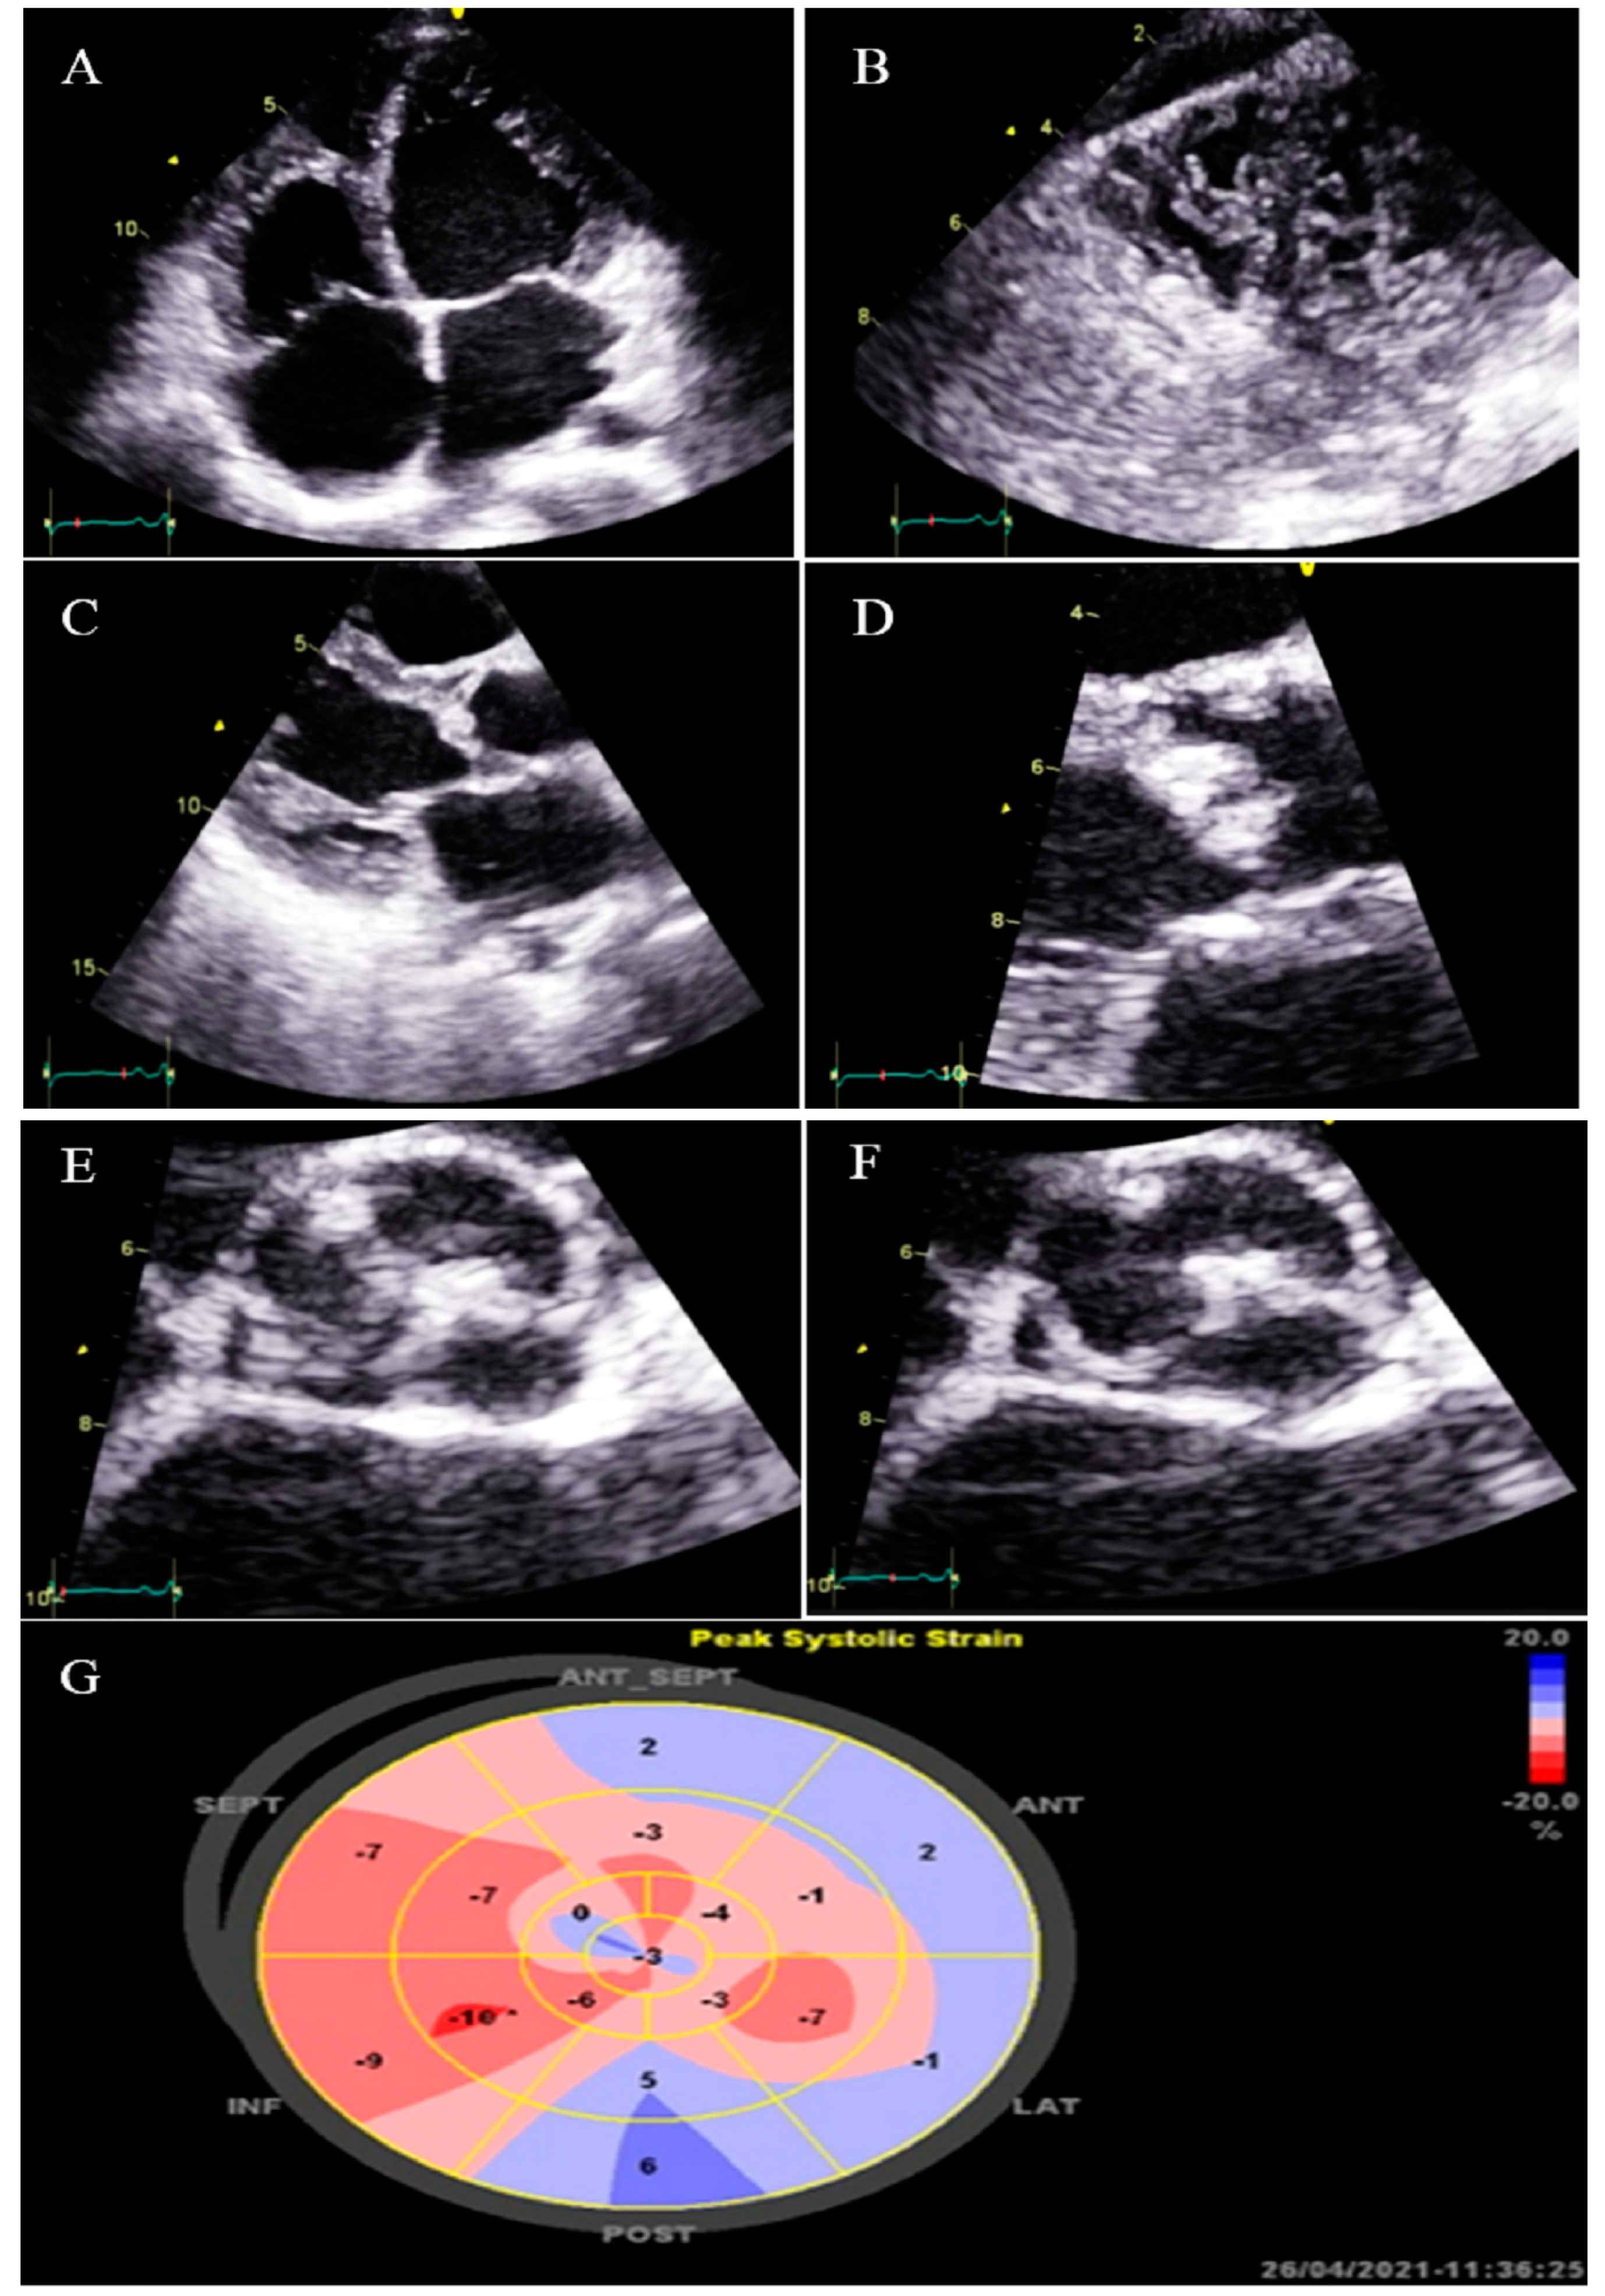

2.12. Case #12. BVNC with a Dilated Aorta

| 12 | M | 58 | History of palpitation and shortness of breath on heavy exercise | − | BVNC, LVEF = 55% | Dilated aorta | − | + | carvedilol; 6.25 mg BID | Doing well |